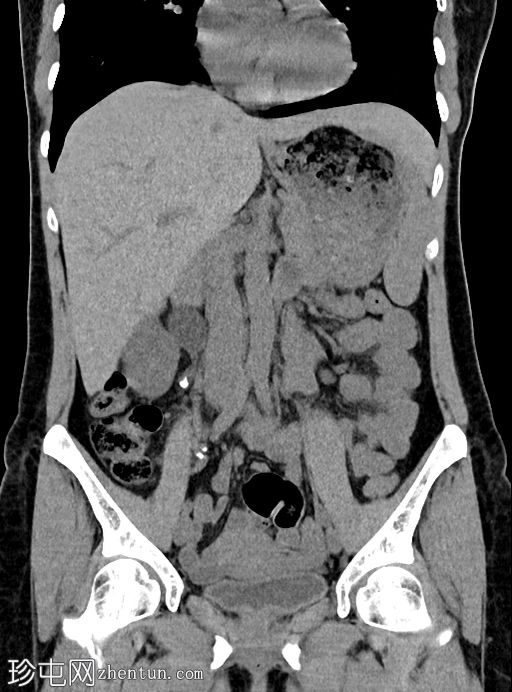

冠状位肾部

排泄期

右侧输尿管上段可见一小块高密度结石(约1500 HU)

近端输尿管及右侧肾盂肾盏系统中度扩张

右髂窝内可见多个小钙化结节,符合钙化淋巴结的特征